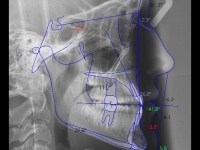

El paciente E.A. acude a nuestra consulta por diastema inferior y ausencia de contactos en los sectores laterales.

El stripping consiste en la reducción interproximal del esmalte entre los dientes posteriores y anteriores, así obtenemos espacio para alinear los dientes apiñados.

Chica de 17 años tratada en 1 año con stripping en los dientes inferiores